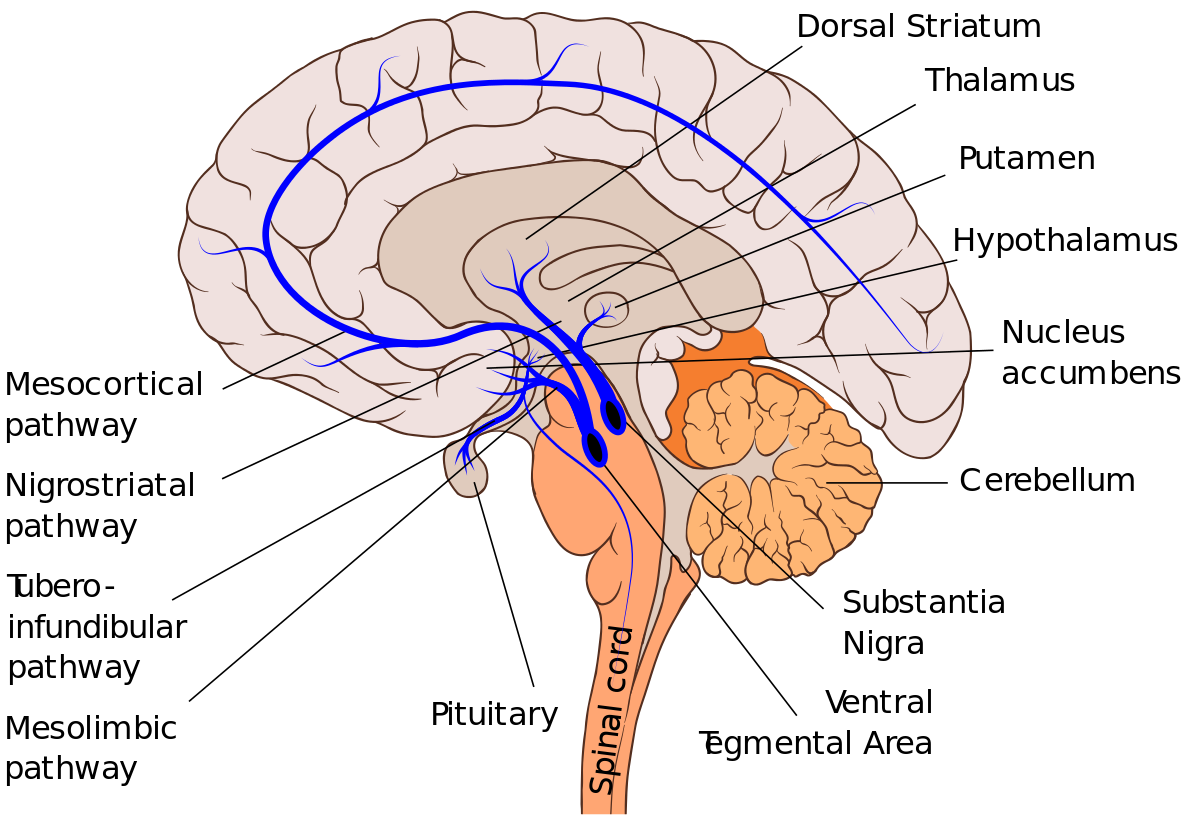

The emotional resilience of an individual is closely tied to the quality of their sleep. Studies [3] have revealed that sleep is essential for regulating emotional responses and processing negative experiences. The amygdala, a key player in emotional processing, undergoes a recalibration during sleep, helping individuals better cope with stress and emotional challenges. Disruptions in sleep patterns have been linked to heightened emotional reactivity and an increased risk of mood disorders.

Sleep plays a crucial role in memory consolidation, a process in which newly acquired information is stabilized and integrated into existing knowledge networks. The hippocampus, a brain region vital for memory formation, is particularly active during specific stages of sleep, such as rapid eye movement (REM) sleep. Research [2] suggests that the reactivation of neural pathways during sleep strengthens synaptic connections, contributing to the consolidation and organization of memories.